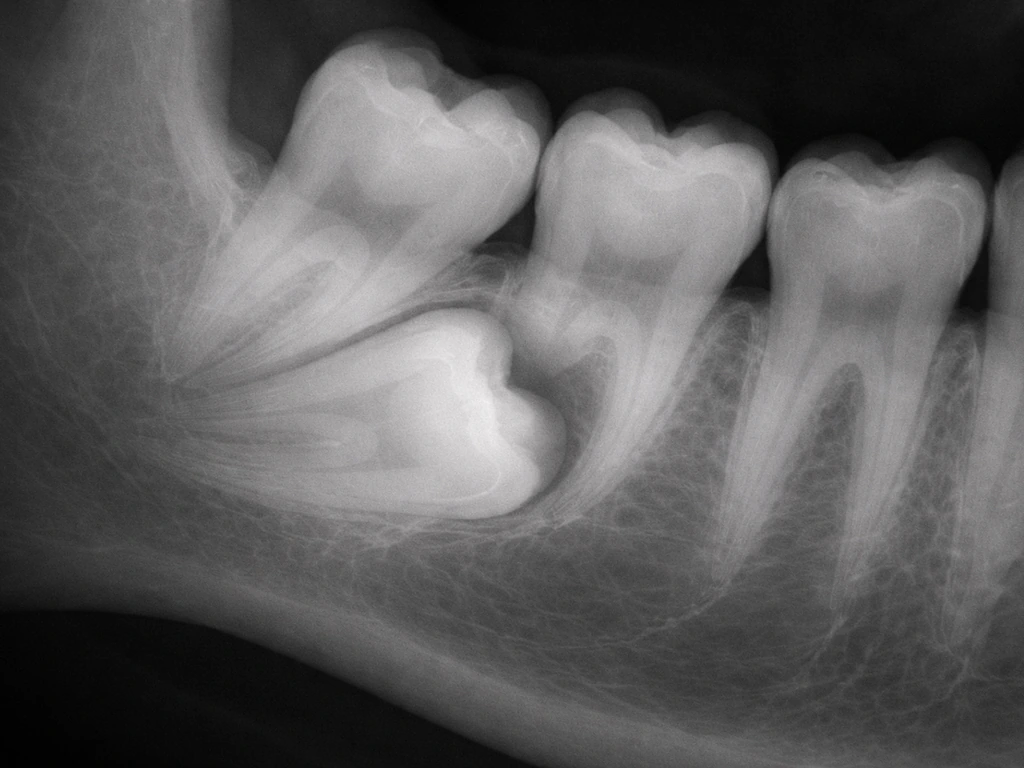

An impacted tooth is one that fails to erupt fully because it is blocked by another tooth, bone, or soft tissue. Impacted teeth are not growing somewhere new; they are stuck where they formed and either stay buried or, occasionally, find an abnormal path to the surface. Impacted canines, for example, can sometimes erupt through the roof of the mouth rather than through the normal gum position. Syndromes like cleidocranial dysplasia (caused by mutations in the RUNX2 gene) are associated with large numbers of impacted and supernumerary teeth, sometimes dozens of them visible on panoramic X-rays.

The single most useful preventive step for catching abnormal tooth development early is a panoramic radiograph around age 7 to 8, which most pediatric dentists recommend anyway as part of orthodontic screening. This one image can reveal supernumerary teeth, impacted teeth, odontomas, and cysts before they cause symptoms or damage neighboring teeth. If you are an adult who has never had a full-mouth X-ray series and you have noticed odd dental history (teeth that never came in, asymmetric eruption, unexplained swelling), it is worth asking your dentist about getting one now.